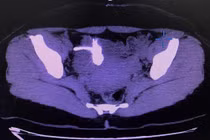

(khoahocdoisong.vn) - Bệnh nhân N.T.N. (60 tuổi, Hà Nội) bị đau bụng nhiều hạ sườn trái, đại tiện táo và co thắt khoảng 4 ngày trước khi vào viện. Bệnh nhân đến Bệnh viện T.Ư Quân dội 108 thăm khám, chụp X-quang và được các bác sĩ phát hiện dị vật hình chữ T nằm trong lòng đại tràng, xuyên thủng đại tràng.